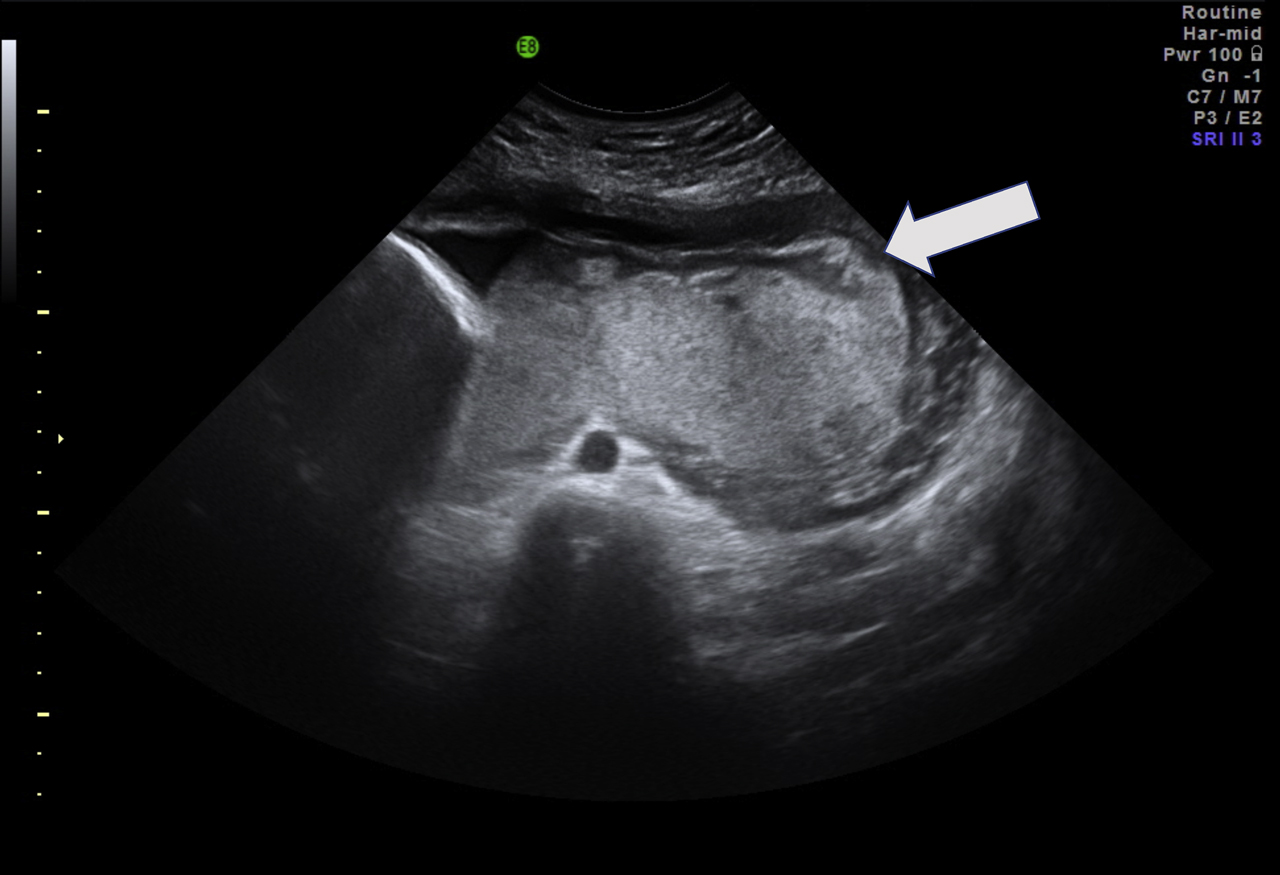

We report a case of a growth restricted fetus caused by a circumvallate placenta as a rare finding which may be associated with further severe pregnancy complications. It can be diagnosed antepartum by ultrasound screening or as a visual diagnosis after birth (Figures 2 and 3).

Thickened placenta with atypical echogenicity at 28+2 weeks of pregnancy. Arrow: circumvallate margin.

The ultrasound showed a growth restricted fetus with an estimated weight of 815 g (<third percentile) and oligohydramnios. Umbilical blood flow was reduced with an absent end-diastolic flow in the umbilical artery while the blood flow in the uterine artery and in the middle cerebral artery were normal. Fetal movements were present. The placenta appeared enlarged with a spherical shape.

Radiographic features of the circumvallate placenta can be an abnormal placental thickness (>3 cm), a peripheral echodense rim or an irregular placental edge (placental “shelf”). Similar features can also be found in other placental abnormalities: The most important radiographic differential diagnosis is amnion sheets and amniotic bands.